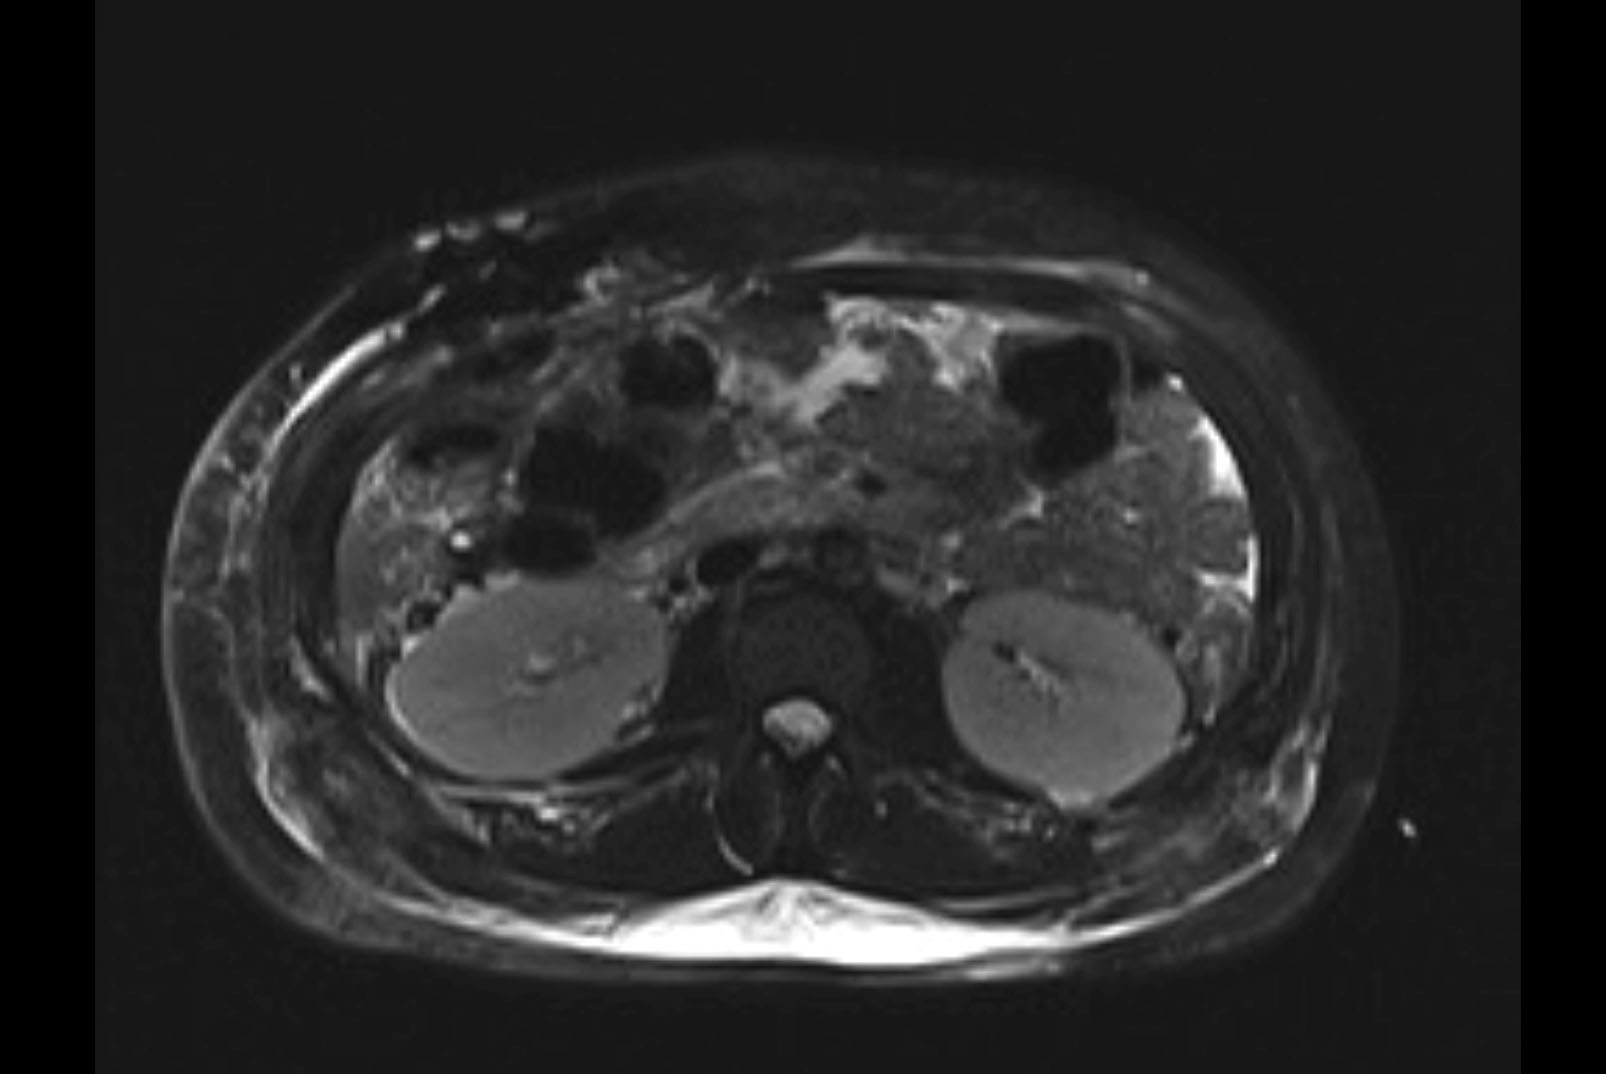

MRI T1

MRI T2